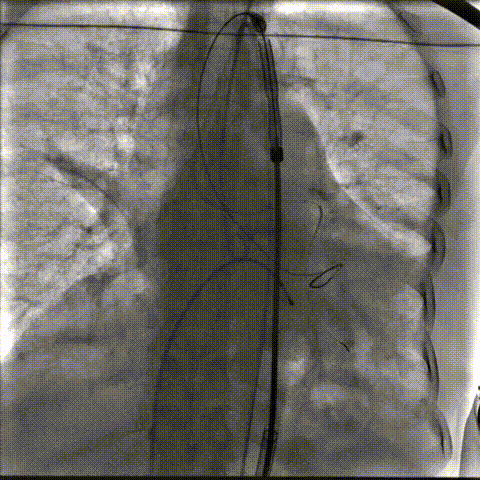

LCA保护下18mm球囊预扩,扩张充分,瓣叶向LCA开口偏移;输送器过弓顺利。

瓣环下精准定位稳定释放,瓣膜工作位造影考虑瓣叶推挤LCA阻挡临界状态,释放“烟囱支架”。

瓣膜稳定脱钩,20mm球囊后扩,“烟囱支架”Kissing,后扩后支架形态改善。